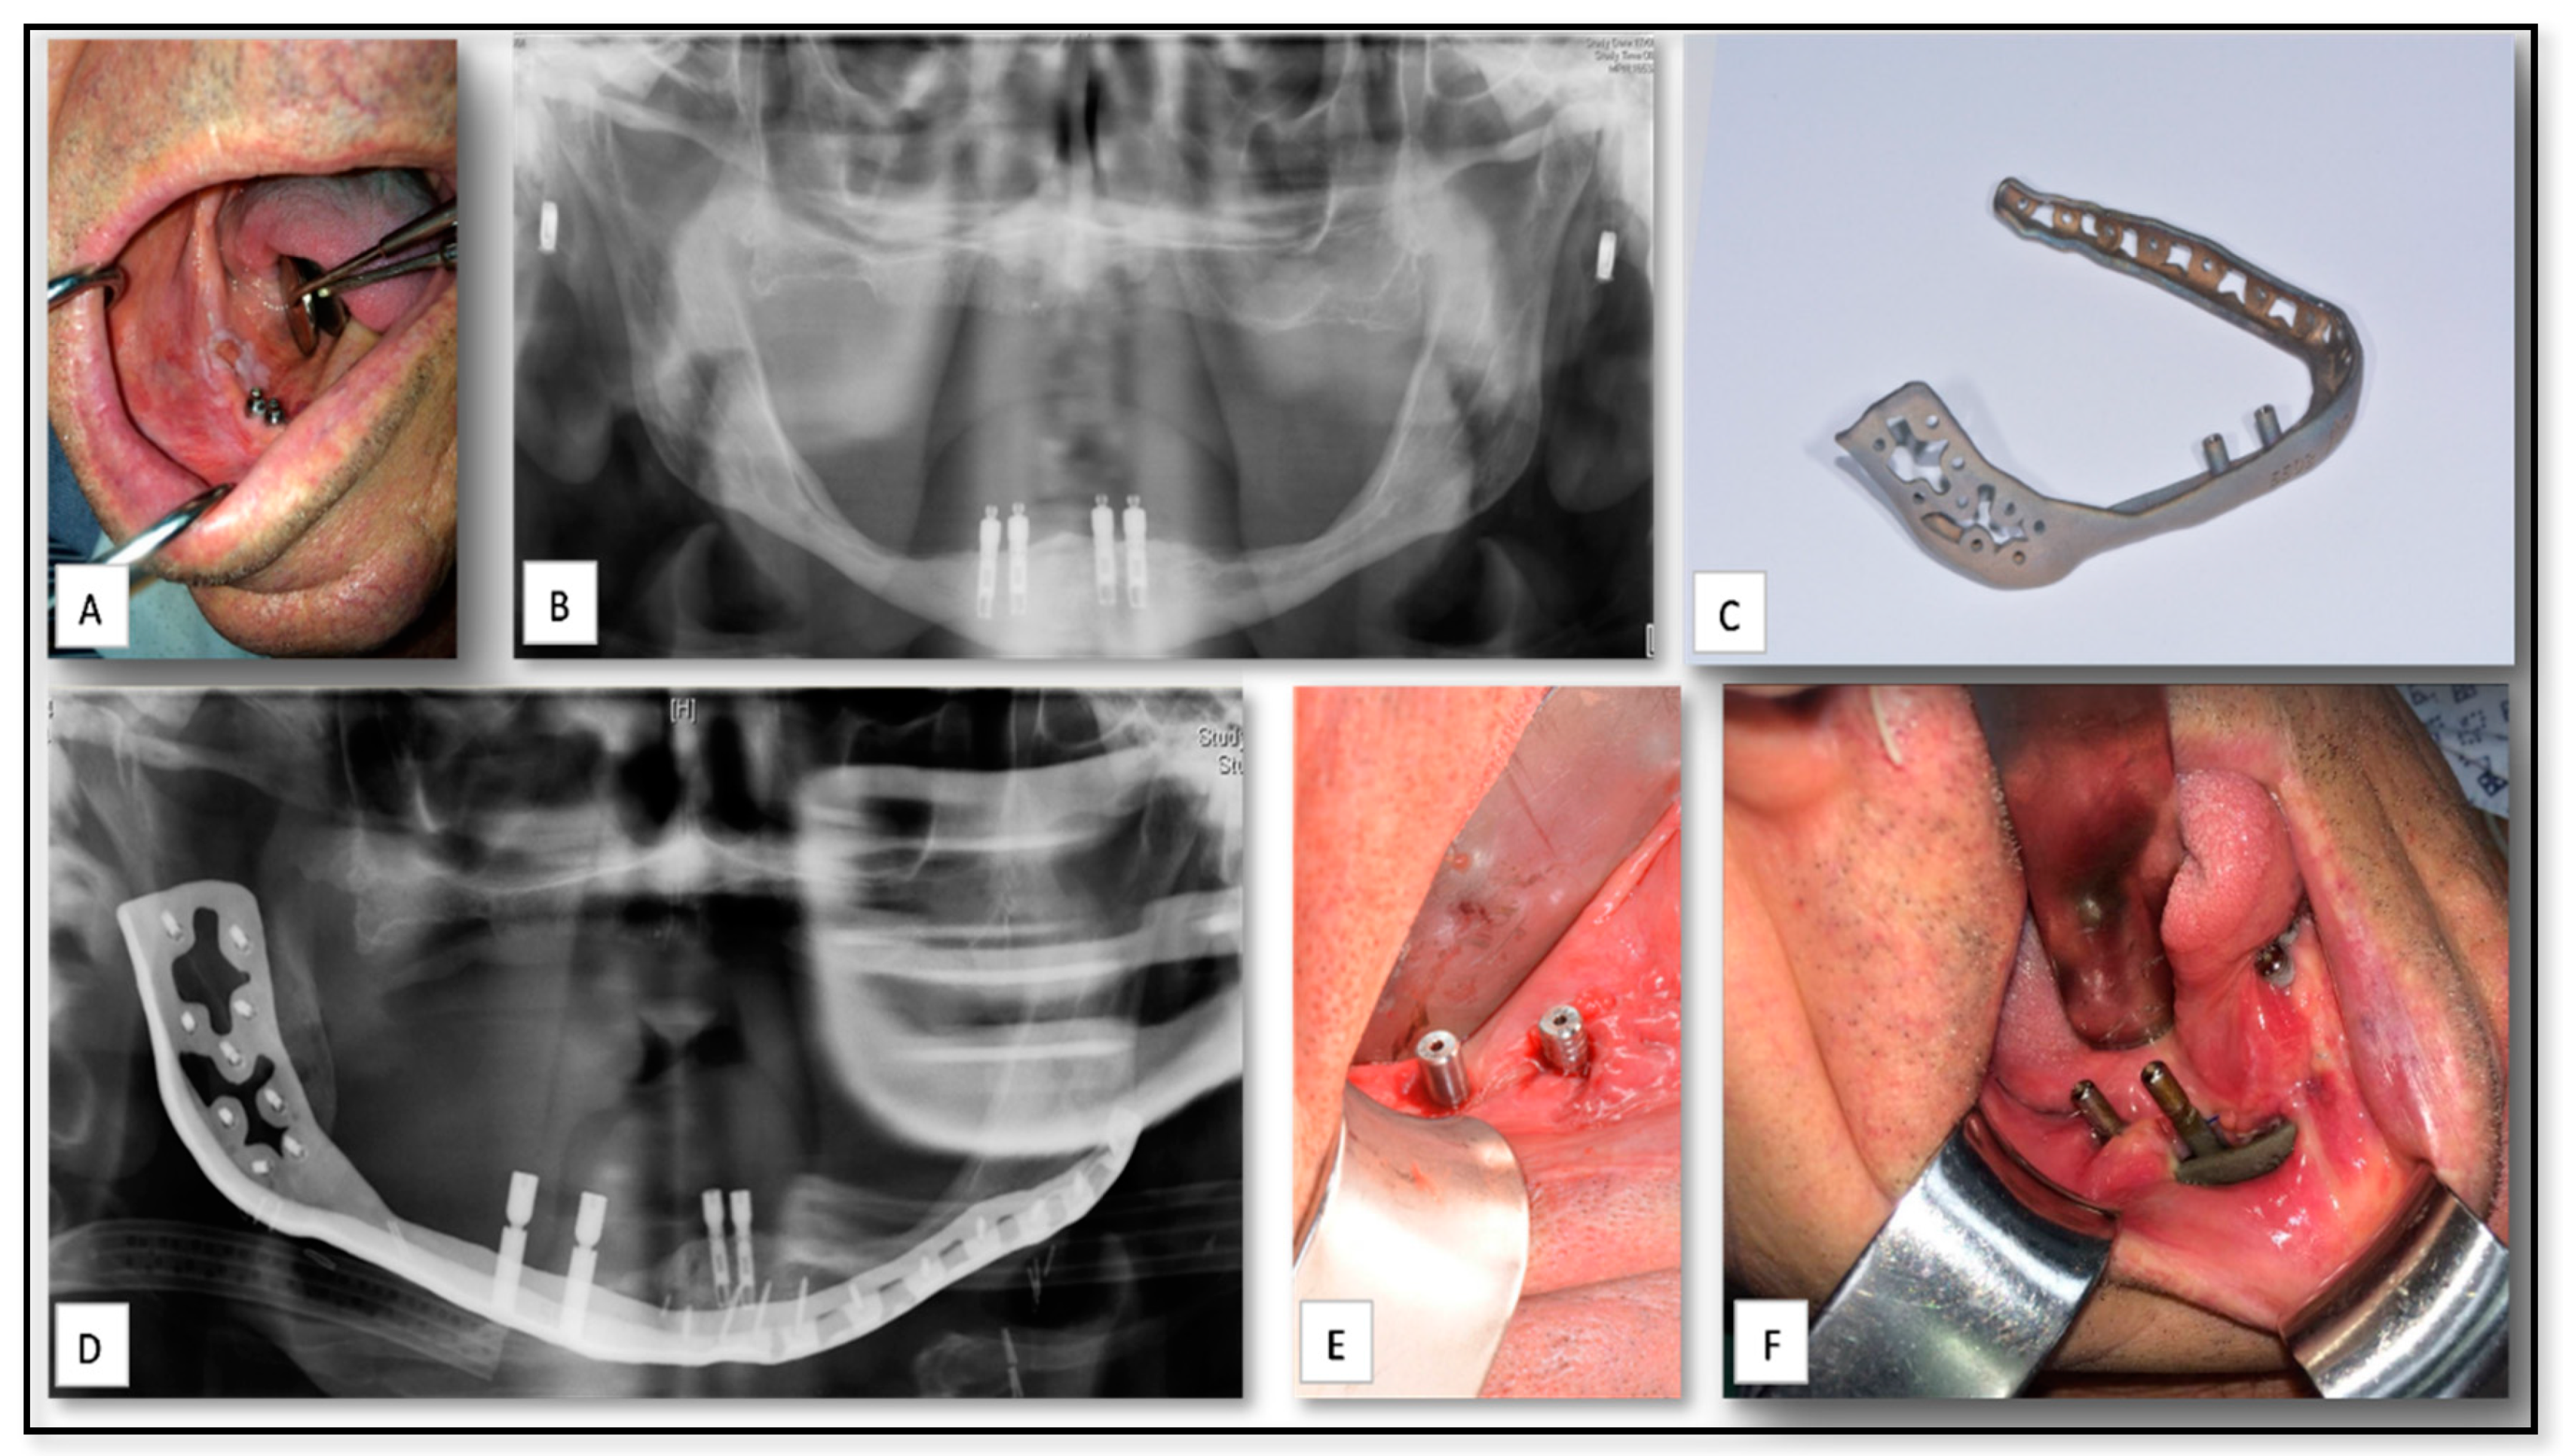

5.2. AM for of Pre-Prosthetics Patient-Specific Implant (PSI) Manufacturing

5.3. AM for PSI Manufacturing for Delayed Correction of Post-Traumatic Defects